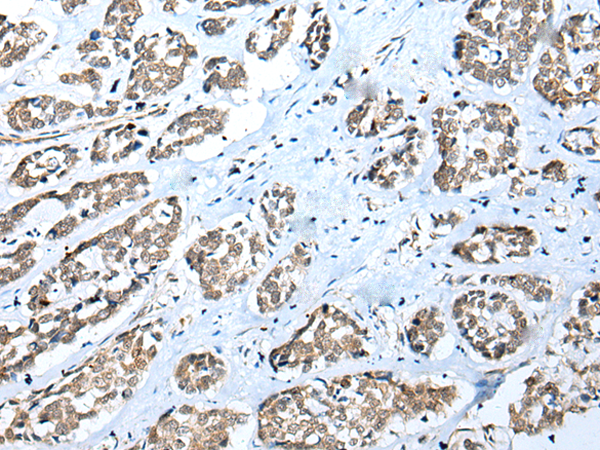

分类: 科研抗体货号: P09096别名:应用: IHC反应种属: Human